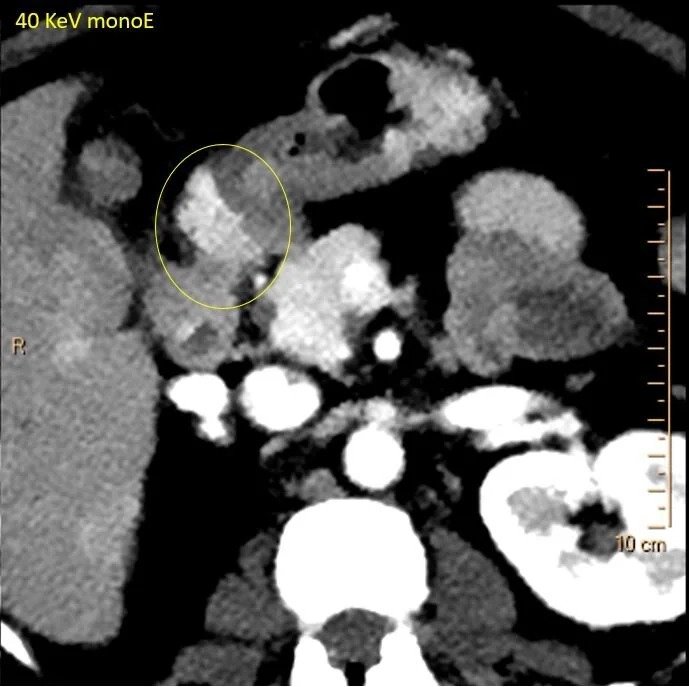

On the lower keV images, there is an intensely enhancing mass at the undersurface of the pylorus/duodenal bulb. This is nicely depicted on the iodine map. On spectral curves, this is identical to the pancreas.

40 keV monoE: See the enhancing nodule at the undersurface of pylorus/duodenal bulb